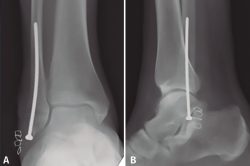

Tornillo intramedular de peroné

La osteosíntesis del peroné con tornillo intramedular se trata de una técnica descrita hace más de cien años(51). Los beneficios principales de esta técnica son la menor agresión y la disminución de complicaciones de las partes blandas(17,52,53). Otros beneficios de la técnica endomedular son evitar la prominencia subcutánea de material, evitar la penetración de tornillos en la articulación del tobillo y evitar el riesgo de lesión de los tendones peroneos(17,52).

En 2017, Loukachov(17) realiza una revisión sistemática de 6 estudios retrospectivos recientes sumando un total de 180 pacientes, incluyendo fracturas inestables en pacientes ancianos con osteoporosis y mal estado de partes blandas. En esta revisión sistemática, la tasa de infección fue del 0,6%, la necesidad de retirada de material del 1,7% y la tasa de pseudoartrosis del 1,1%, con una reducción anatómica en el 93,3% de los casos. Loukachov obtiene resultados similares en su propia serie y concluye que se trata de una técnica segura y adecuada, con una baja tasa de complicaciones de partes blandas y sin el incremento del coste del implante del clavo intramedular de peroné(17), entre los cuales no hemos encontrado estudios comparativos. Ebraheim(53), en una serie de 45 pacientes con mal estado de partes blandas (9 de ellos con fractura abierta) y/o comorbilidades con riesgo para complicación de la herida (15 de ellos con diabetes), tratados con tornillo intramedular de peroné percutáneo, presenta una tasa de complicaciones del 4% (una pseudoartrosis y una retirada de material por molestias), sin presentar ninguna infección de la herida lateral.

Bankston(52), en un estudio biomecánico comparativo en fracturas de tipo supinación-rotación externa no conminutas, no encuentra diferencias en la resistencia a la torsión en comparación con la osteosíntesis convencional (placa de tercio de caña y tornillo interfragmentario). La limitación de esta técnica es que el tornillo intramedular no puede mantener de forma fiable la longitud del peroné en fracturas conminutas(52), a diferencia de los nuevos diseños de clavos intramedulares de peroné(54).

La osteosíntesis endomedular del peroné está descrita con diferentes tipos de tornillos, siendo los más utilizados en la literatura los tornillos de 3,5, 4,2 o 4,5 mm(17). Nuestra preferencia personal es la utilización de un tornillo cortical de 3,5 mm largo, de 80 a 120 mm de longitud (de la caja de pelvis), debido a la mayor flexibilidad del implante y la capacidad de adaptación al canal medular(52,55) (Figura 4). Este tornillo puede permitir incluso la reducción del desplazamiento lateral del fragmento distal del peroné con el punto de entrada adecuado en la punta del peroné(55). Esta técnica también permite espacio para añadir un tornillo para la estabilización de la sindesmosis(17,53).